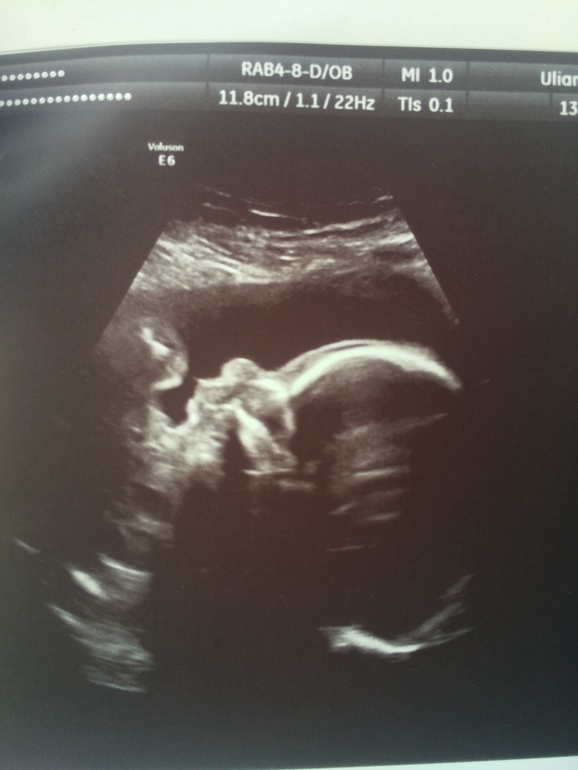

УЗИ, КТГ, доплерОт УЗИ, а конкретнее от узистки я не в восторге.. Есть хорошие новости и не очень.. Под кат Малыш соответствует 23 неделям.. Развиваемся хорошо☺️ Весим 492 грамма..😍😍😍 носик 6,2мм, ЧСС 156..)) БПР 56мм, ЛЗР 73 мм, ОГ 204мм, ОЖ 173мм..)) количество вод нормальное..)) все тьфу тьфу..)) ☺️малыш махал кулочками, шлепал губами, потом нахмурился, вытянул губы в трубочку и отвернулся)))🙄пришлось погулять, погладить, чтобы он повернулся обратно..))) Наконец то поднялась плацента!😊 В принципе все отлично, за исключением ШЕЙКИ! 25мм, закрыта на всём протяжении... У меня паника.. Завтра записываюсь к своему платному врачу..что то надо делать..очень страшно.. Ну и фото моего котёнка❤️❤️❤️

В 12+0 - первый скрининг. В 15+2 из за тонуса сама ходила. В 20+0 второй скрининг. В 23+5 УЗИ с прицелом эхо-кг..)) теперь в 30 только)))